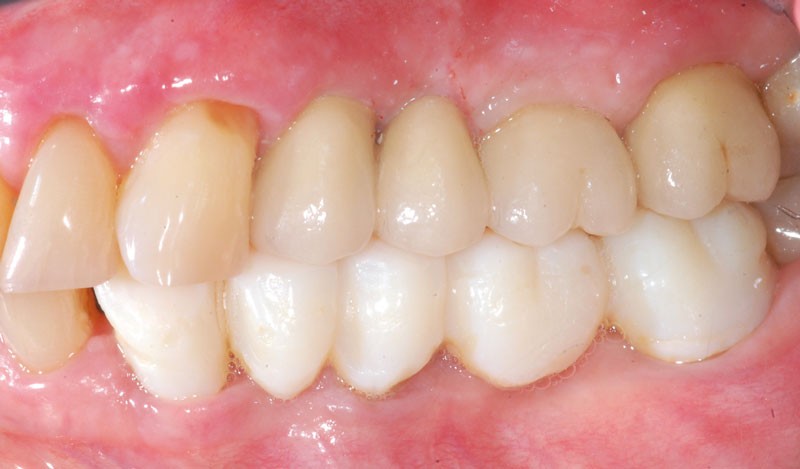

Le bridge 24-26 céramométallique et la couronne unitaire sur 27 sont réalisés. Les piliers CFAO sont transvissés sur les implants, puis les éléments céramo-métalliques sont posés. Le résultat montre un parfait respect du projet prothétique en fonction de la courbe occlusale obtenue avec le bridge transitoire réalisé avec le ProtempTM 4 et une adaptation parfaite.